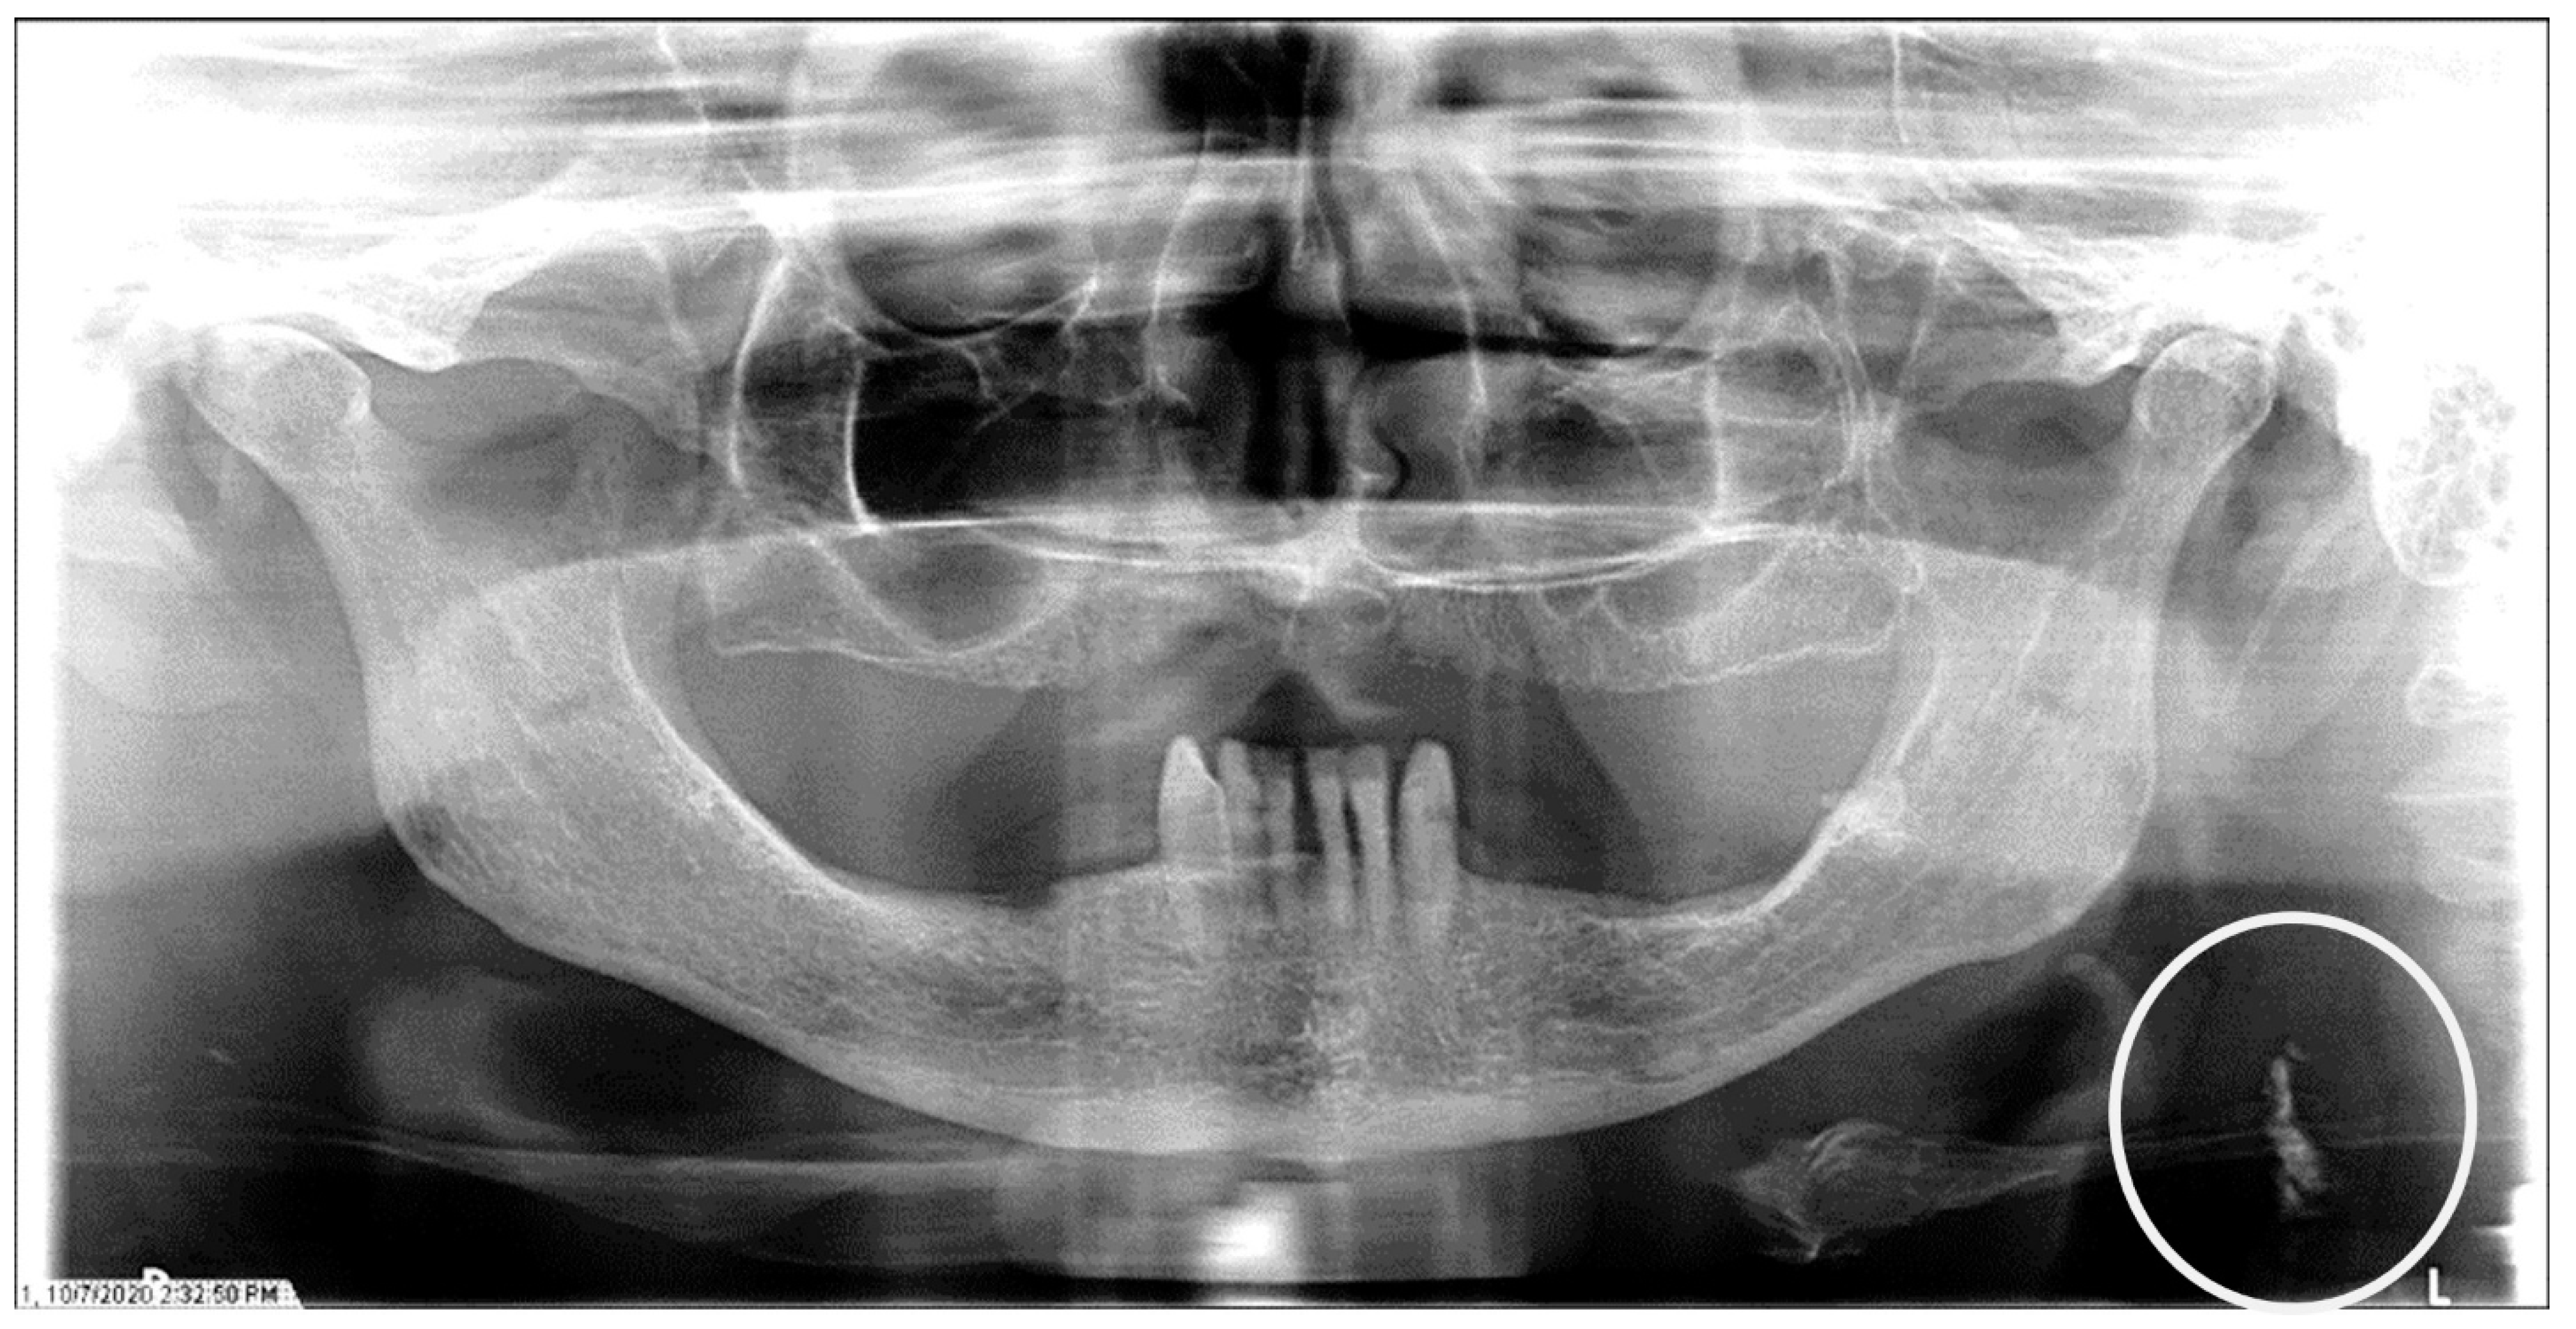

The characteristics of the CAC patients are presented in Table 1. Between 2014 and 2023, there were 559 patient records with the terms “carotid artery calcification” or “carotid” or “calcification of the carotid artery” noted. After the panoramic radiographs were reviewed, 314 patients were confirmed to have a diagnosis of CAC (including 26 patients with a history of carotid endarterectomy). The remaining 245 patient records were excluded because of the absence of detectable CAC on PRs and the absence of PRs to review. The ages ranged from 29 to 92 years, with a median of 68 years. CAC was most prevalent (39.5%) in the seventh decade of life. There were 168 (53.5%) female and 146 (46.5%) male patients. The median age of the female patients was 68 years, and the median age of the male patients was 69.5 years. The calcifications were identified unilaterally in 168 (53.5%) patients (88 females/80 males; mean age: 67.8 years) (Figure 1 and Figure 2) and bilaterally in 146 (46.5%) patients (80 females/66 males; mean age: 68.6 years) (Figure 3, Figure 4 and Figure 5). The DMFT index in the CAC patients ranged from 8 to 32 (mean = 26.6). The frequency of patients with CAC with a history of hypertension, hyperlipidemia, diabetes mellitus, CVA, and CAD was 86.2%, 57.6%, 30.7%, 15.5%, and 28.7%, respectively.

Figure 5.

The panoramic radiograph of a 53-year-old male patient with a medical history of hypertension and hyperlipidemia showing bilateral carotid artery calcifications (CACs) during a comprehensive dental examination. The CACs are encircled by a white line.